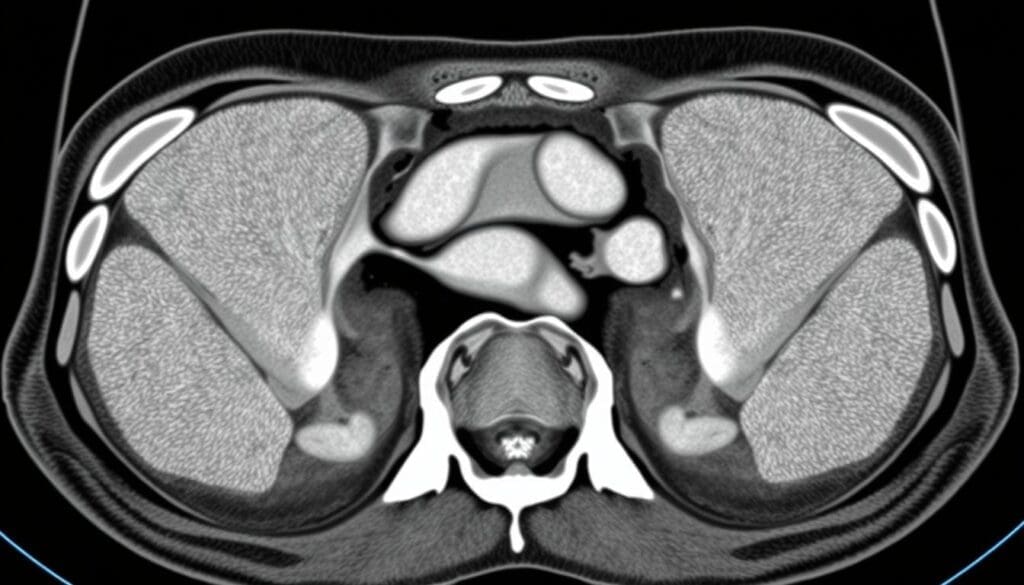

CT scans are key in finding inguinal hernias. They use X-ray technology to show the body’s inside. This helps see the small details of the inguinal area and spot hernias.

CT scans mix X-rays and computer tech for detailed body images. The patient lies on a table that moves into a scanner. The scanner spins around, taking X-ray pictures from many angles.

These pictures are then put together into slices. This gives a full view of the body’s inside.

For finding hernias, special CT scan rules are followed. These rules help make the images clearer and more accurate. The Valsalva maneuver is often used. It’s when the patient tries to push air out with their mouth closed and nose pinched.

This makes it easier to see hernias. Thin-section imaging and multiplanar reconstructions also help. They let doctors see the inguinal canal and nearby areas well.

This helps them find hernias, know their size, and where they are. It also helps figure out any problems they might cause.

For surgeons, clear images before surgery are key. CT scans give a full view of the hernia and what’s around it. This helps spot any issues that might come up during surgery.